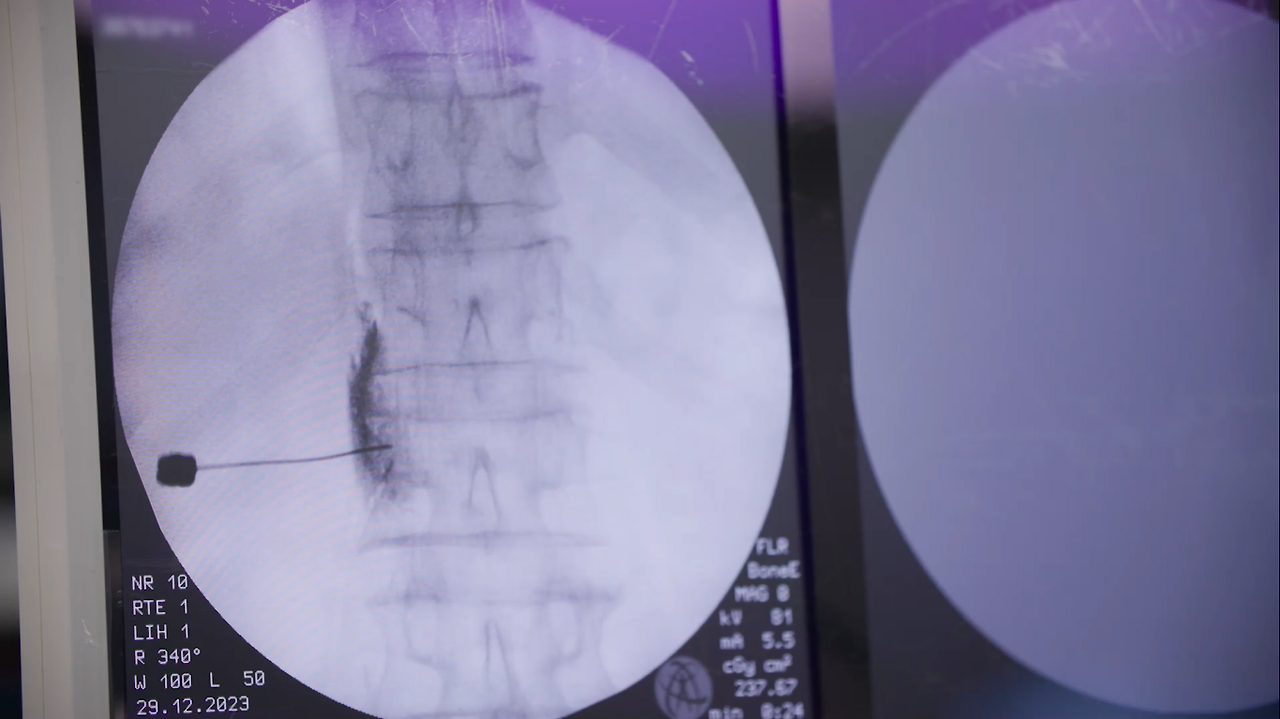

- 척수 자극기 삽입술 : 경막외 공간에 삽입한 전기 자극기로 미세한 전류를 흘려보내 통증을 절감하는 치료

■ 국내 최초 소아 ‘척수 자극기 삽입술’을 받은 10대 청소년의 만성 통증 극복기

2년 전 넘어짐 사고 이후 CRPS(복합 부위 통증 증후군) 진단을 받은 15살 백승윤 군. 난치성 통증 질환으로 걷기가 어려워 지팡이와 휠체어의 도움을 받아야만 했다. 의료진은 고민 끝에 ‘척수 자극기 삽입술’을 결정했다. 척수 자극기 삽입술은 척추를 둘러싼 경막외 공간에 전기선을 넣어 통증이 유발되는 부위에 전기 자극을 가해서 통증 신호를 방해하는 치료법이다. 의료진은 환자가 만 14세가 될 때까지 기다렸다가 지난해 국내 최초로 소아 환자의 척수 자극기 삽입술을 시행했다. 치료 후 일상을 되찾기 위해 노력하고 승윤 군은 어떤 미래를 꿈꾸고 있을까.